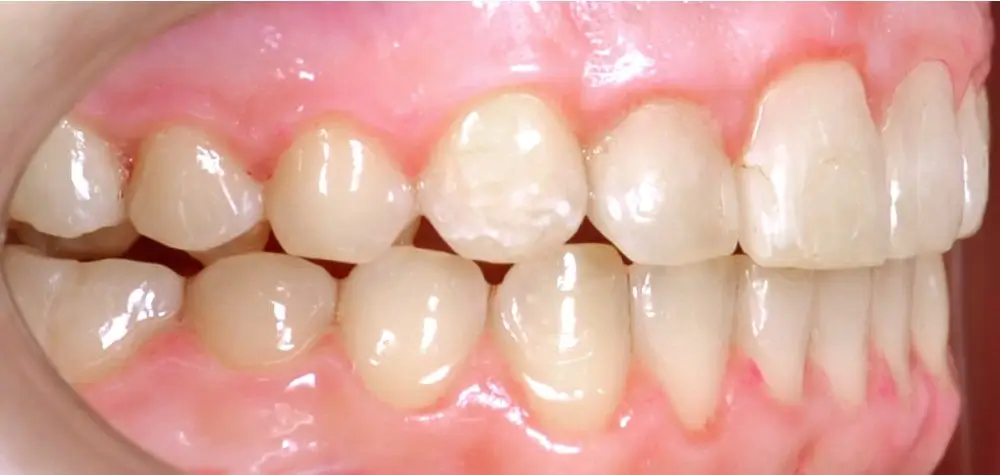

Открытый прикус - Кейс 2

Эффективность устранения дефекта прикуса посредством элайнеров FlexiLigner.

22

Количество кап НЧ

Количество кап ВЧ

Результаты лечения